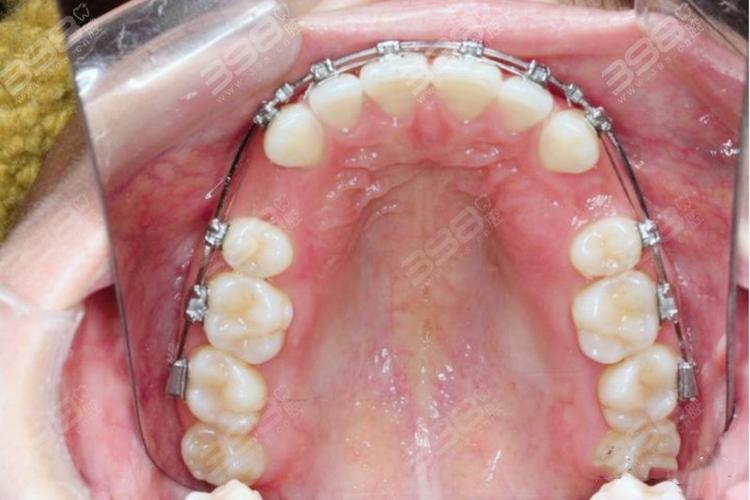

拔牙后开始戴矫正器(如传统托槽矫正器、隐形矫正器),需注意:

- 口腔清洁:矫正期间牙齿清洁难度增加,需使用正畸牙刷(小头刷毛)、牙线(穿过托槽下方)、冲牙器,每天至少刷牙3次,每次3分钟,预防龋齿和牙周炎。